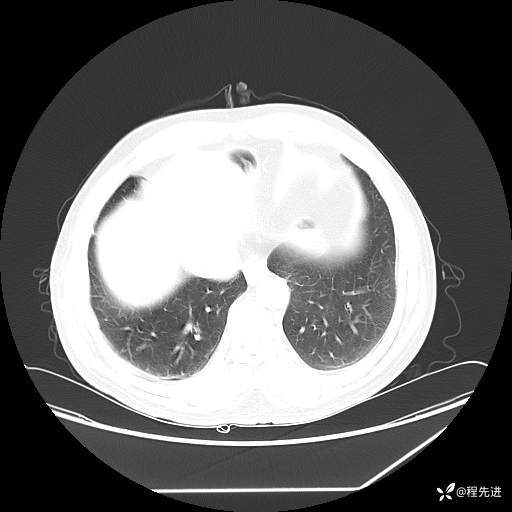

患者性别:男

患者年龄:57岁

简要病史:声嘶2月余

CT平扫+增强: